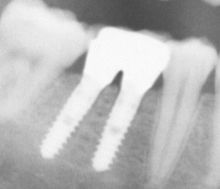

Roscados

Presentan aspecto de tornillo, con una rosca en su superficie, con lo que se consigue aumentar la superficie de contacto del implante con el hueso.